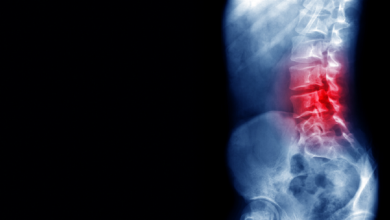

روسيا.. عقار مضاد لالتهاب الفقار القسطي يجتاز بنجاح أولى الاختبارات السريرية

أعلن الأكاديمي سيرغي لوكيانوف، رئيس جامعة بيروغوف الطبية الوطنية للبحوث، أن عقارا لعلاج الفقار القسطي، اجتاز بنجاح مرحلة الاختبارات السريرية…